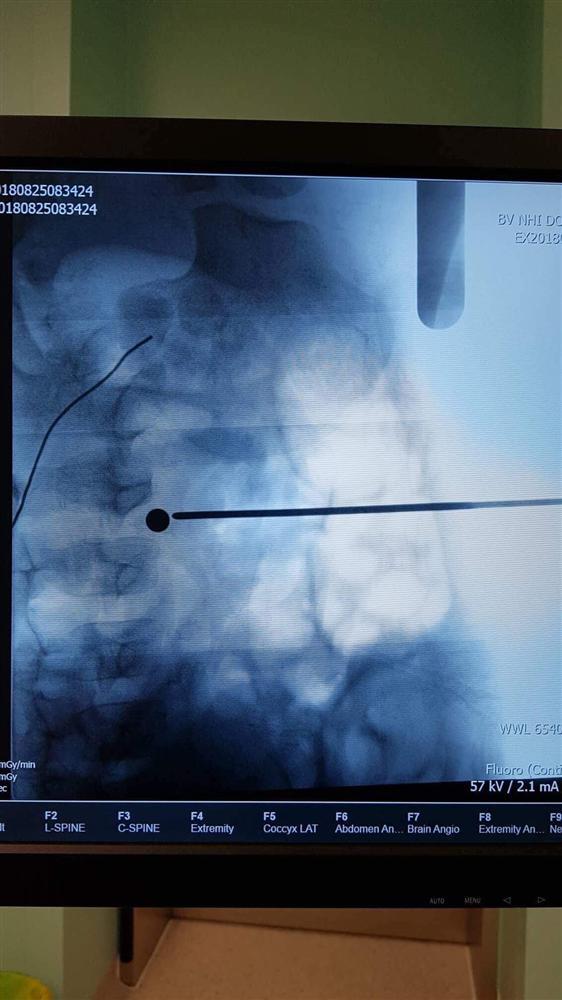

Phim chụp X-Quang cho thấy viên đạn tròn nằm ở ngay đốt sống L4-5.

ThS.BS Tạ Huy Cần, trưởng ekip mổ cho biết: “Viên đạn xuyên thẳng thấu vùng thắt lưng, nằm trong đĩa đệm đốt sống L4 - 5, ngay trước rễ thần kinh tọa và thần kinh đùi. Nếu đạn đi chếch ra sau 1 chút sẽ đứt hệ thống rễ thần kinh này, nguy cơ yếu liệt cao, nếu ra trước một chút sẽ đi xuyên qua bó mạch chủ ngay chỗ chia mạch chậu gây nguy hiểm tính mạng”.